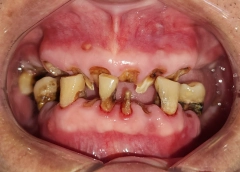

• Tình trạng răng trước đây:Mất hết răng cả 2 hàm, tiêu xương hàm

Chú Nguyễn Hải từng dành nhiều thời gian để tìm hiểu và lựa chọn nha khoa trồng răng Implant khiến mình thật sự an tâm. Bởi với chú, sức khỏe hàm răng rất quan trọng. Chú không muốn gặp bất kì biến chứng nào khi không may làm răng tại một địa chỉ kém chất lượng. Cuối cùng, chú Hải đã quyết định đặt niềm tin vào nha khoa I-Dent. Vậy lý do tại sao?

Từ đó, chú Hải đã quyết định sẽ thực hiện Implant tại I-Dent. Bởi chú nhận ra chất lượng quan trọng hơn chi phí rất nhiều, và kết quả trồng răng cuối cùng đã không phụ lòng mong đợi của chú.

Chú Hải có được hàm răng mới chắc khỏe, ăn uống thoải mái mà không phải kiêng cữ như trước. Nhờ đó mà sức khỏe ngày càng tốt hơn, chú cũng thêm vui vẻ, yêu đời.